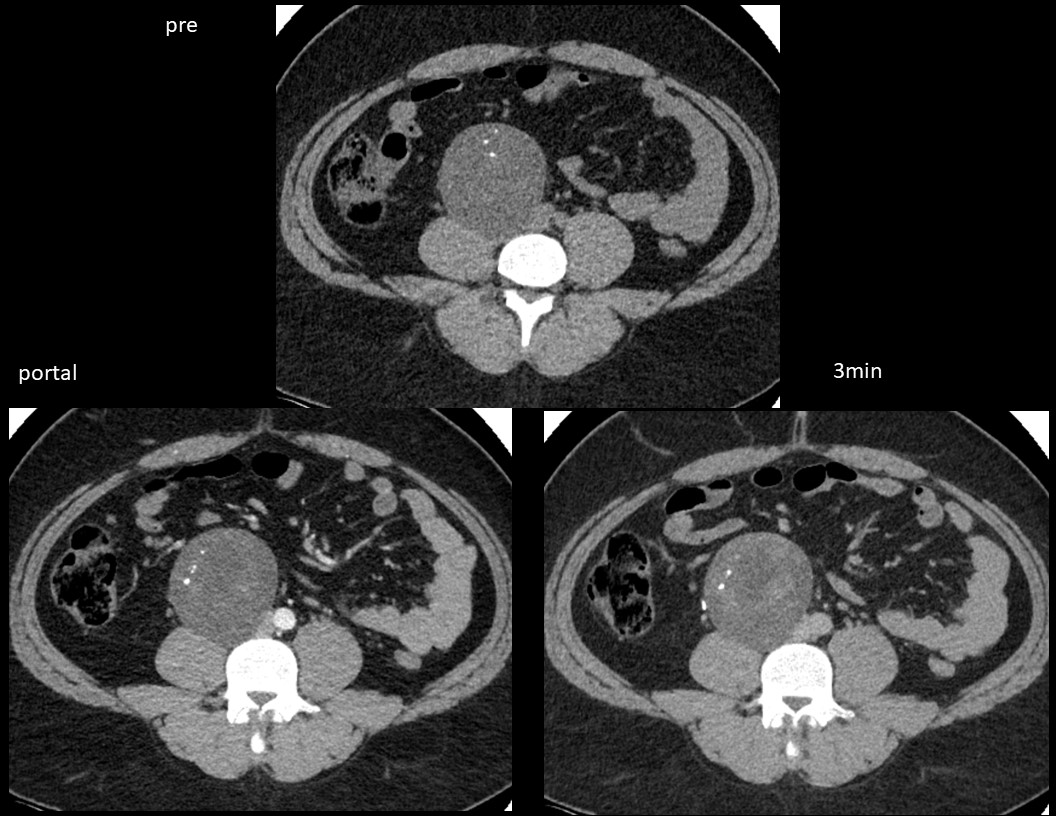

No.160

M / 60 Rt. Inguinal mass

URORADIOLOGY 조범상 충북대 2880 2024-02-07